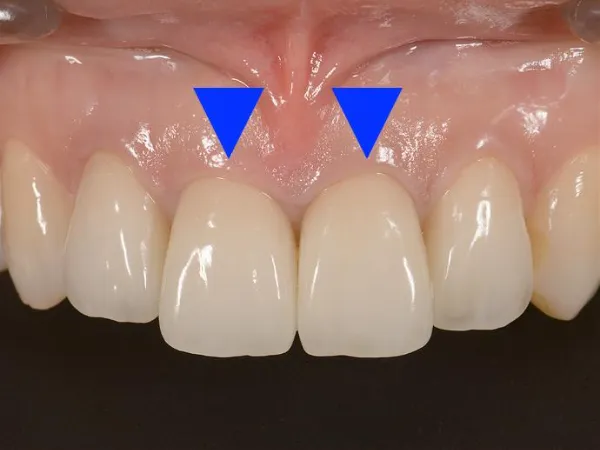

オールセラミック セラミック(陶器)でできたクラウンです。 セラミック(陶器)でできたクラウンです。 | メリット ・虫歯、歯周病になりにくい ・自然な仕上がり ・変色しない ・アレルギーなし デメリット ・割れる可能性がある ・値段が高い |

ジルコニア 当院1番のオススメです! 当院1番のオススメです! | メリット ・虫歯、歯周病になりにくい ・自然な仕上がり ・変色しない ・アレルギーなし ・強度が高い ・オールセラミックより値段が安い デメリット ・銀歯やメタルボンドより値段が高い |